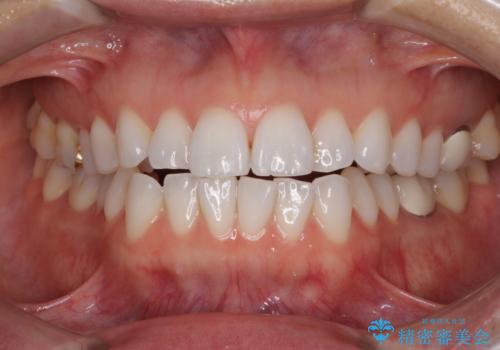

[ 前歯開咬 ] 前歯が噛んでいない マウスピース矯正治療

![[ 前歯開咬 ] 前歯が噛んでいない マウスピース矯正治療の症例 治療後](https://seimitsushinbi.jp/wp/wp-content/uploads/2022/11/IMG_2488-500x350.jpg?v=1668218373)